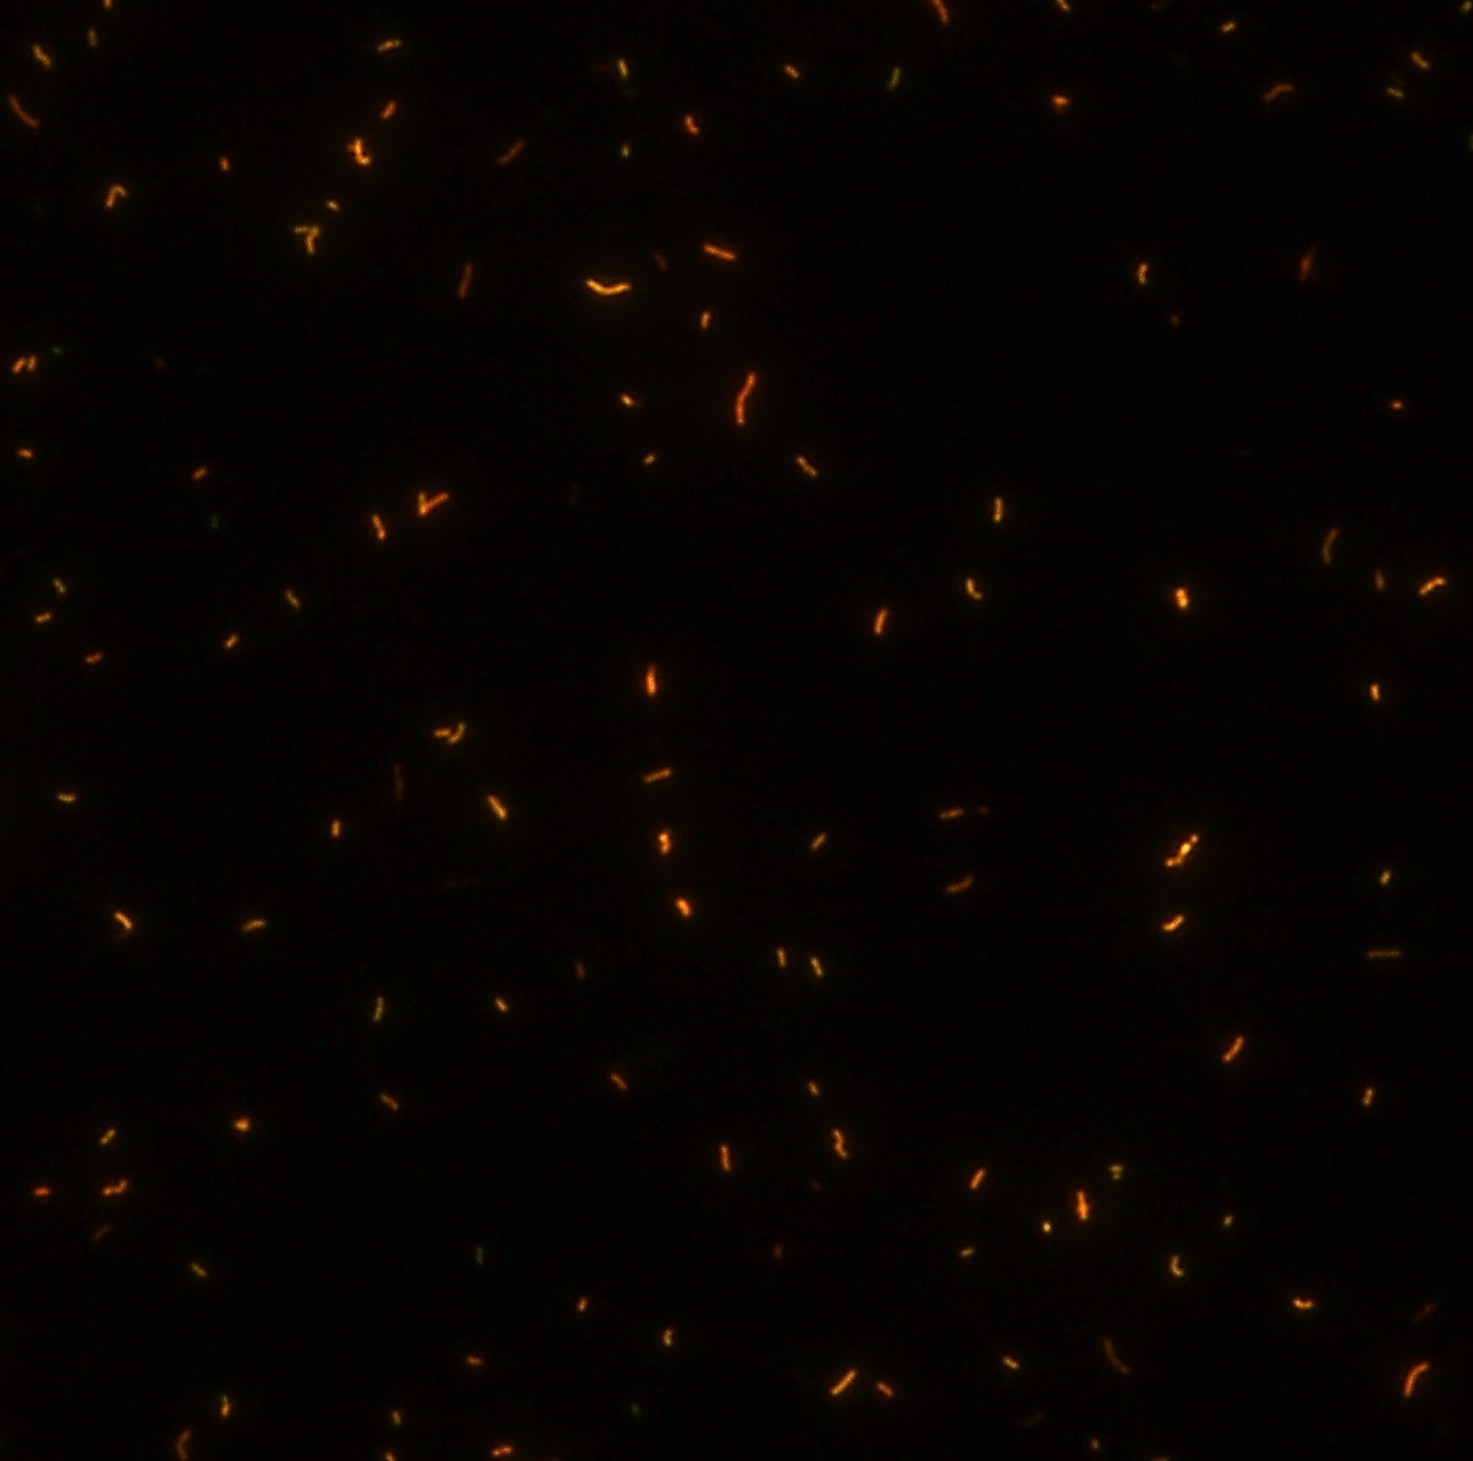

顯微染色技術(shù)是檢測(cè)結(jié)核桿菌方法之一。分枝桿菌細(xì)胞壁中含有分枝菌酸,其可以與染料牢固結(jié)合,具有“抗酸性”的特征。熒光染料金胺-羅丹明在染色中與抗酸生物細(xì)胞壁內(nèi)的分枝菌酸相結(jié)合,并耐受酸醇(脫色劑)清洗脫色。反染色劑高錳酸鉀被用來(lái)顯出染色生物。AFB(熒光)染色試劑盒設(shè)計(jì)既可用于自動(dòng)染色機(jī),也可用于手工染色。產(chǎn)品穩(wěn)定性好,染色效果佳。

染色結(jié)果 (熒光法×400)

用于分枝桿菌、諾卡菌等細(xì)菌抗酸染色,包括熒光染色。